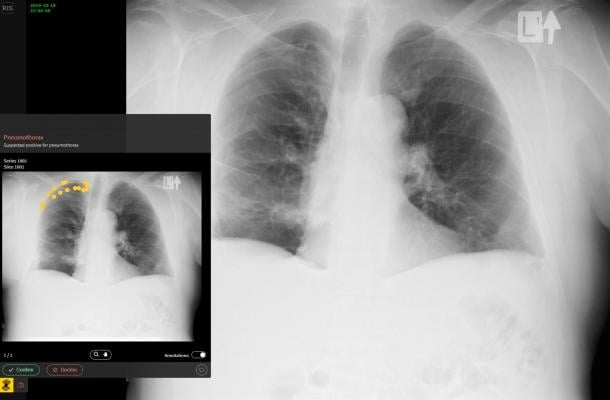

In addition to the zero-footprint PACS, the company’s Exceed RIS customers will also be able to enjoy the benefit of Zebra Medical Vision's Triage solutions running as a safety net for all radiologists on call, flagging the presence of acute conditions on head CTs and chest X-rays.

Helping to cover both outpatient and in-patient settings, Zebra-Med’s Triage solution prioritizes scans based on the emergency level and allows radiologists to address prioritized scans in a timely manner. Scans are forwarded automatically to Zebra-Med’s cloud based solution for analysis, the server then sends an alert of the positive cases directly to the Emergent Connect worklist for prioritizing, thus saving physicians more than 85 percent of the time taken to reach the acute condition, such as a brain bleed in a head CT scan.